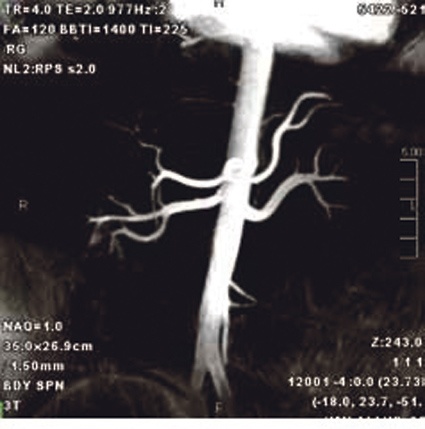

Die Leistungsfähigkeit eines MRT wird oft in Zahlen und Fakten fixiert, was aber nur einen Teil der Wahrheit mitteilt. Dies sind im Wesentlichen die Gradientenstärke und die Anzahl der Messkanäle. Hier kann der Titan 3T mit bis zu 45 mT/m und einer Anstiegsrate von 203 T/m/s aufwarten und steht anderen Systemen der „70-cm“-Klasse in nichts nach. Er kann aber auch mit den häufig völlig ausreichenden 30 mT/m bestellt werden und später bei Bedarf (nur unter Austausch der Gradientenverstärker) auf 45 mT/m aufgerüstet werden. Zusätzlich kann man den Titan 3T auch in einer 16- oder 32-Kanal-Variante erhalten, wobei die 32-Kanal-Variante nur zwingend vorgeschrieben ist, wenn man auch die forschungsorientierte 32-Kanal-Kopfspule nutzt. In allen anderen Fällen nutzt der Titan 3T die im FOV vorhandenen Spulenelemente, kombiniert sie intelligent und optimiert so die Ausleuchtung der untersuchten Anatomie. Toshiba nennt diese Funktion AS-Compass, weil sie den Anwender bei der Auswahl der Spulenelemente effektiv führt.

Die Leistungsfähigkeit des Vantage Titan 3T wird derzeit bei Toshibas Kooperation mit Prof. Frederik Barkhof, Chef der Neuroradiologie der VUMC (Vrije Universiteit Amsterdam Medical Center), unter Beweis gestellt. In dieser Kooperation werden z. B. neueste Sequenzen zur Untersuchung von MS- und Alzheimer-Patienten entwickelt und optimiert. Ein Ergebnis dieser Forschungsaktivitäten ist eine verbesserte 3D-Double-Inversion-Recovery-Sequenz (3D-DIR) zur verbesserten Visualisierung von MS-Plaques, die schon in Kürze in der neuesten Software-Version für alle interessierten Nutzer zur Verfügung stehen wird. Eine weitere Sequenz aus dem Bereich der suszeptibilitätsgewichteten Sequenzen (SWI) wird zurzeit genauer evaluiert. Denn neben Toshibas sehr empfindlicher FSBB (Flow Sensitive Black Blood)-Sequenz sind die Forscher auch an einer weniger empfindlichen FIBB (Flow Insensitive Black Blood)-Sequenz interessiert, da sie Pathologien mit Eisenanreicherungen weniger stark betont wiedergibt.